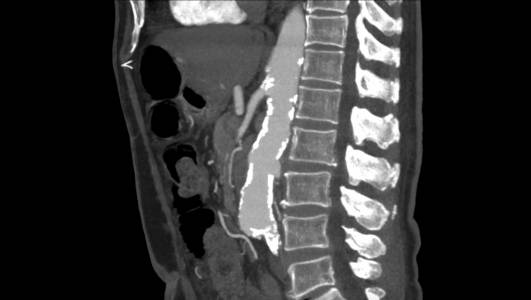

Paciente da entrada hospitalar com dor cardíaca típica sendo diagnosticado com infarto agudo do miocárdio em dezembro de 2019. Apresentava passado de outros três episódios e de revascularização cardíaca com mamária e ponte de safena. Durante internamento paciente evolui com dor abdominal importante sendo indicada realização de tomografia de abdome total que indicou a presença de hematoma intramural da aorta abdominal.

Haja vista a extensa quantidade de comorbidades a cirurgia aberta se fazia de risco muito elevado para o paciente. Este foi então encaminhado para correção endovascular.

O estudo de angiotomografia evidenciou que as artérias iliacas externas e femorais apresentavam-se com muitas calcificações e ponto de estenose mais crítica em artéria ilíaca comum direita. Diante dos achados de imagem, foi optado por endoprotese de aorta abdominal de baixo perfil (Incraft – Cordis).